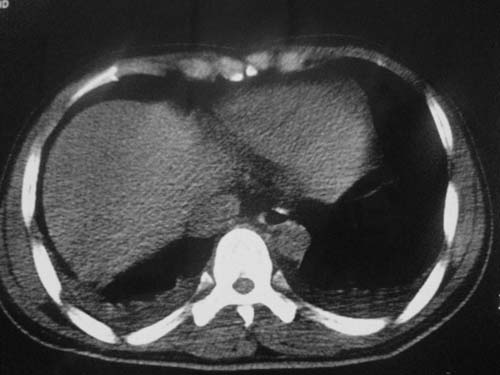

这是第五天拍的ct,纵隔窗我没都传,实在是太费时,请教各位老师,此病人有肺水肿吗?帮忙分析一下